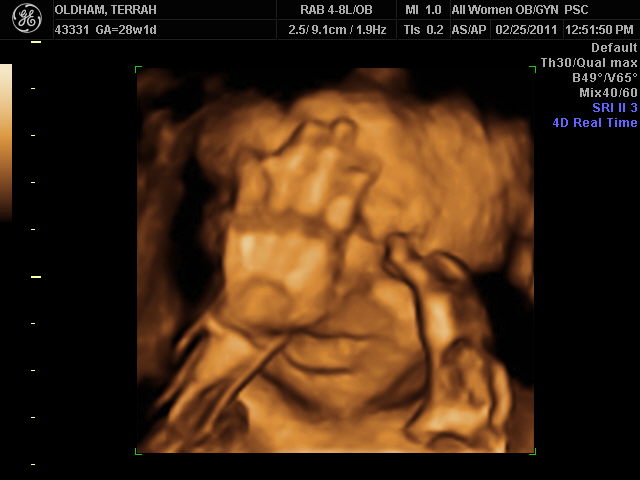

The Oldham S Of Louisville 3d Ultrasound 28 Weeks